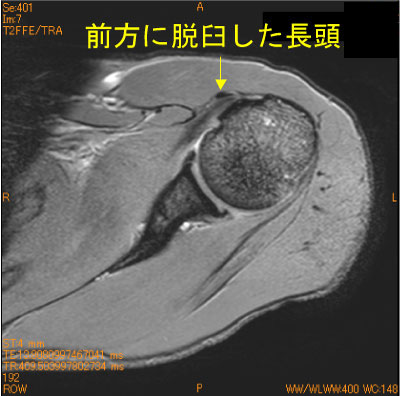

長頭腱前方脱臼-肩関節MRI-

40代男性。20年間のブレークダンス歴(+)。

ダンス時の痛み。結節間溝の横靭帯損傷があり、長頭腱が内側前方に脱臼している。

腱板ばかり見ていると見落とす。

![]() Axial T2*WI 脂肪抑制 |